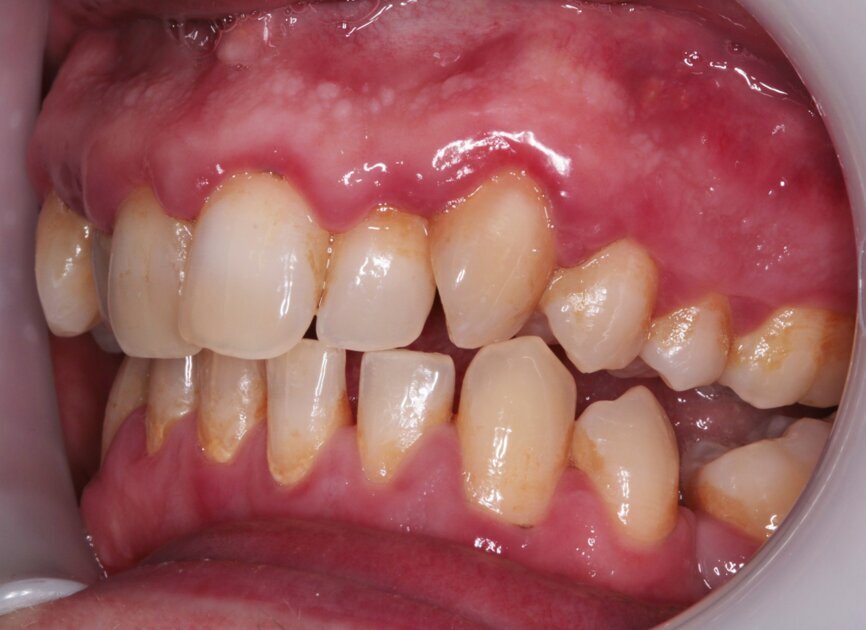

My examination revealed nothing abnormal with his extra- or intra-oral soft tissue, temporomandibular joint or range of motion. However, his oral hygiene was poor, which was not helped by the crowding of his maxillary anterior segment. In addition, tooth #48 was carious. I carried out a full orthodontic assessment (Table 1) and took photographs.

I explained that the maxillary teeth could and should be aligned, as this would likely result in easier cleaning of the teeth, plus it would improve the appearance. The patient and I agreed that the mandibular teeth could remain untouched, as this would keep the cost down, but mainly because they did not bother him. The priority was to stabilise his periodontal condition. A basic periodontal examination Code 3 and heavy bleeding were recorded in each sextant. At that visit, I performed a gross scaling using the ultrasonic scaler and used a model to demonstrate both the use of flossettes and an oscillating toothbrush.

Fig. 3: Pre treatment left lateral

Fig. 8: Post-scaling right lateral view